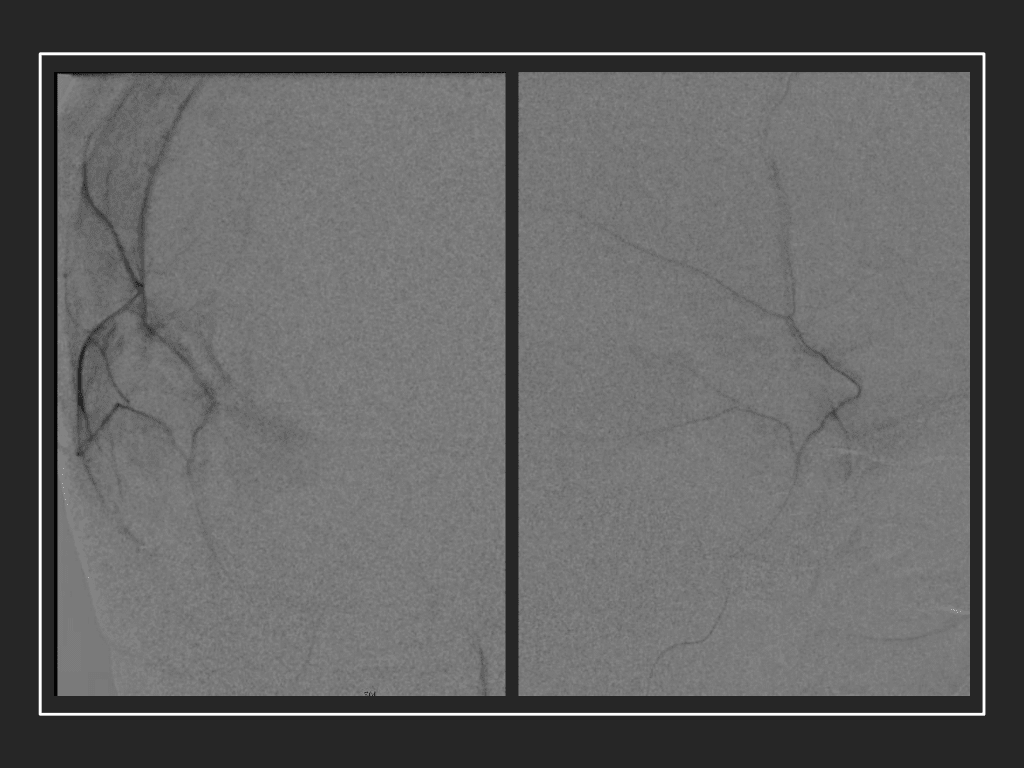

A woman in her 80s developed mild dizziness and headache following incidental trauma working in her garage one day. She presented several weeks later to the ER and was diagnosed with bilateral subdural hematomas, which were initially managed with observation, low dose Decadron, considering the mildness of symptoms, advanced age, and history of CLL with thrombocyptopenia (<100k). Over the next 4 weeks, the collections remained relatively stable with evidence of slight growth (10 to 12 mm thickness, and 2 mm right to left shift) on NCT (Figure 1. A and B).

Figure 1. A) 6 weeks post mild trauma B) 4 weeks post mild trauma demonstrates stable subacute subdural collections with mild growth and sulcal effacement.

CT follow-up at 1 week demonstrates early resorption. 2 weeks post MMA embolization, resolution of the left subdural collection with new small thin acute hemorrhage in an otherwise stable right subdural collection is observed (Figure 3. A and B).

Figure 3. A) 1 week post MMA embolization demonstrating decreasing thickness bilaterally B) 2 weeks post MMA demonstrates resolution on left, with small new acute component on right with overall decreased thickness.

Clinically, the patient improved over the few weeks with the occasional transient twinge of a headache, but resolution of dizziness. Follow-up CT at 10 weeks demonstrated complete resolution of the bilateral subdural hematomas with our patient completely asymptomatic and back to all of her activities of daily living. Considering her history of thrombocytopenia and CLL, we will continue to monitor her into the future and are excited about her progress and recovery. (Figure 4. A and B)

Figure 4. A and B) – 10 weeks following embolization demonstrates complete resolution of bilateral collections both acute and chronic.